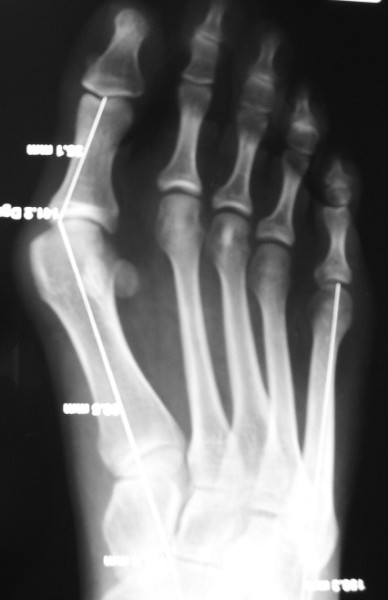

CURE DE L'HALLUX VALGUS

Il en existe de très nombreuses techniques, réparties en 2 types principaux, soit interventions sur les tendons et les ligaments (ex. : Mac Bride), soit, plus récemment et beaucoup plus fréquemment, sur les os, en modifiant par sectionnement leur orientation dans l’espace pour corriger la déformation (ex. : ostéotomie scarf sur le premier métatarsien et sur la première phalange) elle nécessite la mise en place de matériel ou ostéosynthèse (vis et agrafe) qui ne sont pas systématiquement retirés, cette intervention consolide habituellement en 6 semaines.